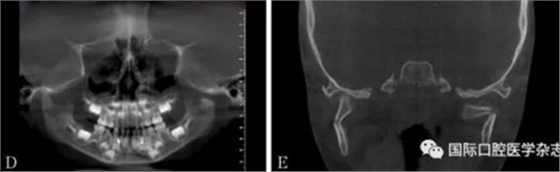

A:術(shù)前開(kāi)口度;B:術(shù)后開(kāi)口度;C:術(shù)前影像學(xué)檢查片;D:術(shù)后影像學(xué)檢查片。

圖 18 關(guān)節(jié)盤(pán)復(fù)位錨固術(shù)前后對(duì)比